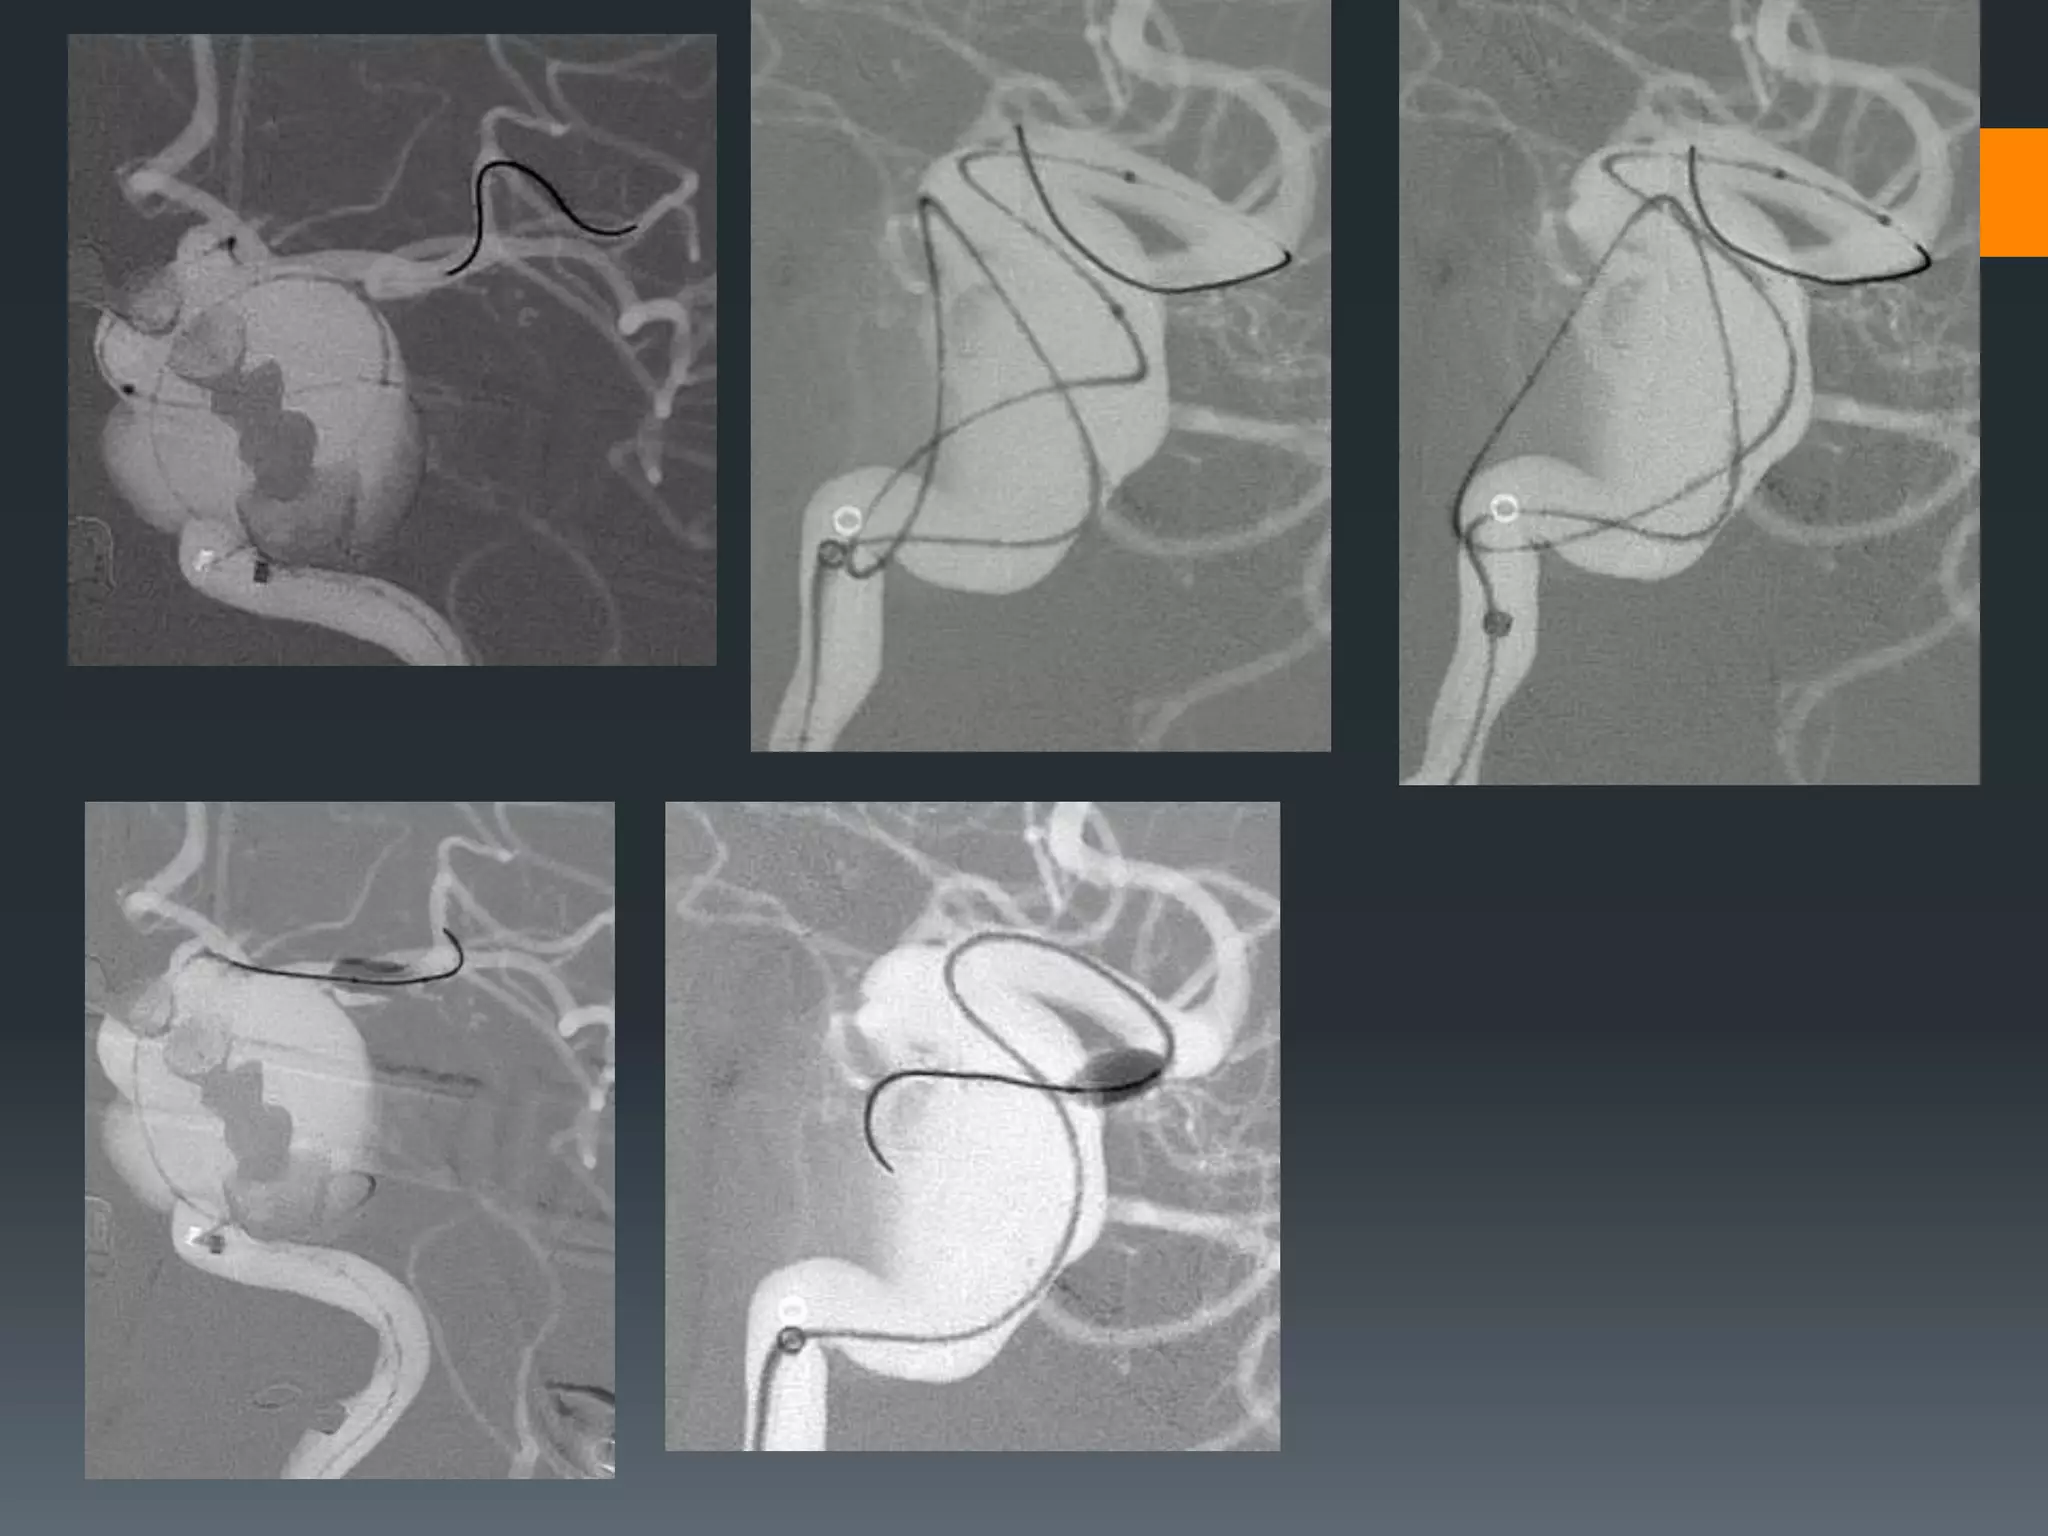

This document discusses tricks and techniques for difficult cannulations during neurointerventional procedures. It outlines strategies for accessing the aortic arch, internal carotid artery (ICA), and areas distal to aneurysms. Long sheaths, distal access catheters, and co-axial techniques are presented as options that have improved cannulation success. Guidance on sheath and catheter selection is provided for different vessel paths. The importance of catheter placement as high as possible in the ICA is emphasized. Reverse curve cannulations are also mentioned. Overall, the document stresses that careful cannulation is critical for procedural success and different strategies may be needed depending on the vessel target.